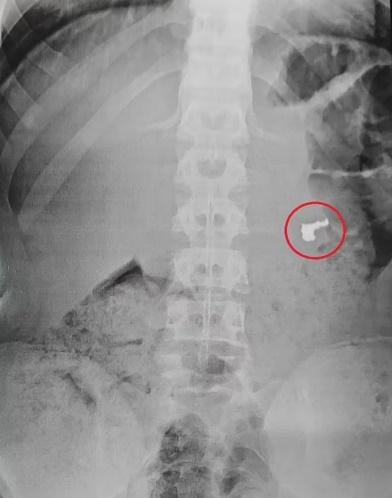

X光檢查在其中一名少年的胃部發現了女遊客被搶去的金鏈。(網上圖片)

綜合報道,事發於周一(24日)在巴西東南部濱海城市Guarujá,3名童黨盯上在海灘上曬日光浴的一名女遊客,其後伺機搶走其金鏈後,踩單車逃離現場。女事主隨即到附近警局報案,附近正巡邏的警員很快就發現及截獲該3名童黨,不過經搜身後卻未發現贓物,幸有警員靈機一觸,將他們押到醫院進行X光檢查,果然在其中一名少年的胃部,發現女遊客被搶去的金鏈。

警方推測,3名童黨擔心人贓並獲,因此將金鏈吞落肚,3名少年被帶返警署落口供後,已獲保釋,稍後將受法律制裁。不過,報道未有提及金鏈是否已經取出。